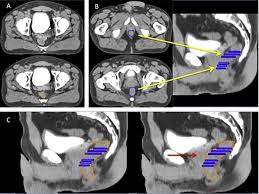

Available Recommendations And Guidelines On Early Detection Of Prostate Download Scientific Diagram

Available Recommendations And Guidelines On Early Detection Of Prostate Download Scientific Diagram from www.researchgate.net